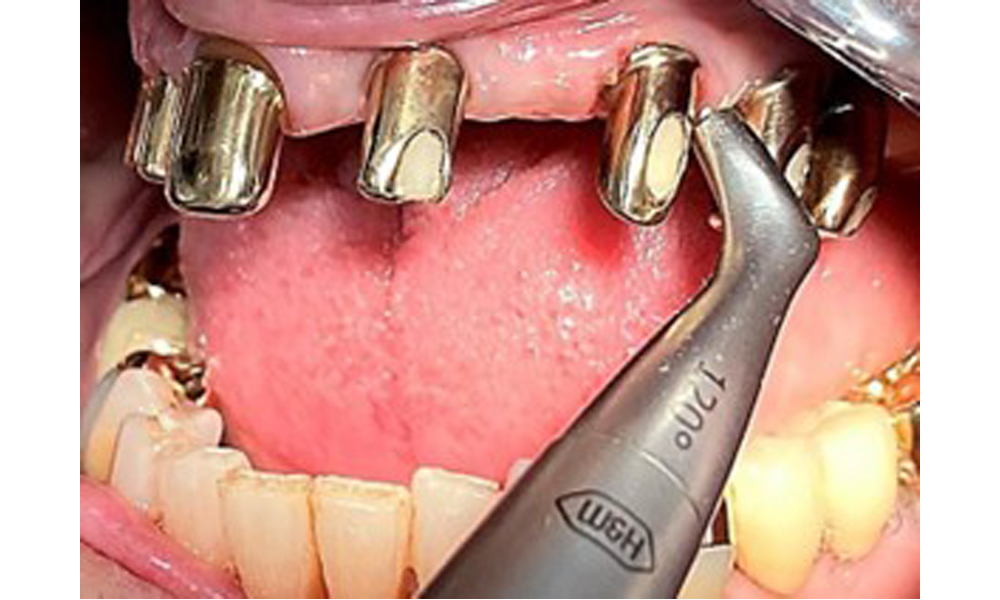

The patient was fitted with a combined removable maxillary telescopic prosthesis more than 25 years ago (Fig. 1, Fig. 2, Fig. 3) and is very happy with her dentures. The patient has an adequate fixed denture for the mandible (Fig. 4).

The dental findings are as follows: Combined removable implant and tooth-supported telescopic prostheses on implants 15, 13, 21, 23, 24, 25 and tooth 11 (Fig. 1, Fig. 2, Fig. 3). The patient was fitted with a fixed mandibular denture. Adequate bridges were present over 37 to 34 and 45 to 47 (Fig. 4), the crown margins were intact and there were no active caries. A composite filling with a marginal gap was present on tooth 43. There was mandibular gingival recession, exposing 1 to 3 mm of root surface. This also applies to 11.